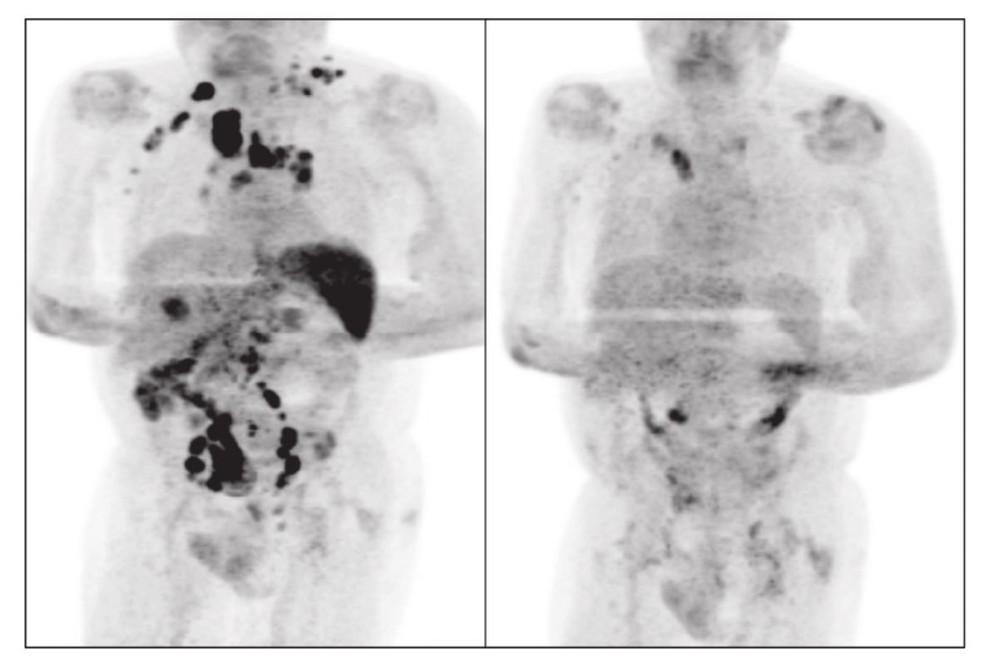

Os autores de um artigo publicado no periódico especializado "British Journal of Haematology" sobre o assunto, Sarah Challenor e David Tucker, reforçam uma hipótese de que a infecção pelo Sars CoV-2 tenha desencadeado uma resposta imune contra o tumor, como já descrito em outras infecções em relação com o câncer em questão.

A "sorte" do paciente decorreu de um processo similar à "imunoterapia", tratamento que utiliza o próprio sistema imunológico do paciente para destruir as células cancerígenas.

Para o oncologista Rafael Cruz, o idoso pode ter passado por uma hiperestimulação do sistema imunológico que ajudou no combate não só do vírus, como também do tumor cancerígeno. Segundo ele, apesar de ser uma situação rara, não é a primeira vez que um caso como esse é registrado pela ciência.